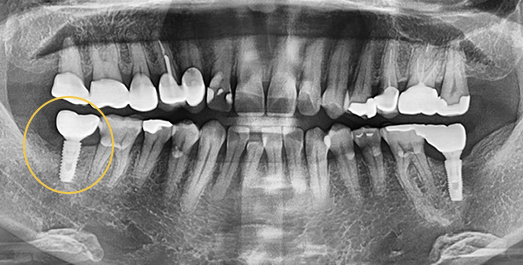

상악동 거상술

잇몸뼈가 없어도 만들어서 식립해드립니다.

상악동은 윗잇몸뼈 위쪽의

코 양옆으로 뻥 뚫려 있는 공간이며, 얇은 막으로 덮여 있습니다.

위쪽 어금니 임플란트를 심을 때 이 부근의 잇몸뼈가 부족하면

임플란트가 상악동을 뚫고 들어갈 수 있습니다. 이를 방지하기 위해 상악동의 얇은 막을 들어 올리고 그 안에 잇몸뼈를 적당히 채워 주는

수술 방법이 상악동 거상술입니다.

• BEFORE: 2021.02.01

• AFTER: 2021.05.13